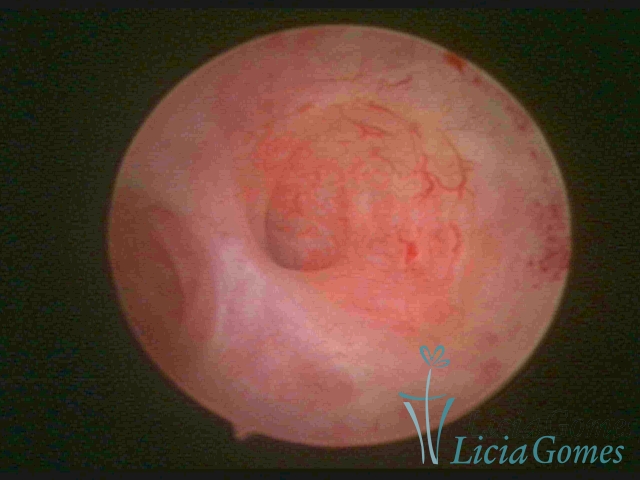

FIBROUS SYNECHIA

Uterine synechiae are scars (adherence) between the surface of the uterine walls, which may occur after the surgical procedure, uterine curettage, or after an inflammatory process in the uterine cavity (endometritis), which may lead to menstrual changes, infertility and obstetric complication such as abortion and premature birth.

• SINÉQUIA TIPO FIBROSA